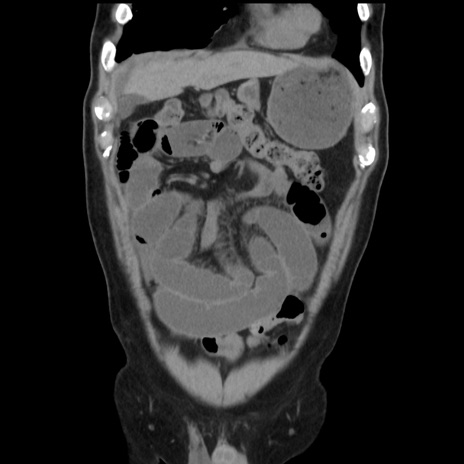

症例16(冠状断像)

【症例】 70歳代男性

【主訴】 腹痛、嘔吐

【現病歴】 約1ヶ月前より間欠的に腹痛と嘔吐あり、当院消化器内科を受診したところCTで多発する肝臓のLDAを指摘され、精査中であった。以降は消化器症状は安定していたが、2日前より嘔気と腹痛があり、同日より排便・排ガスが消失した。改善認めず、 本日、救急外来を受診した。

【身体所見】意識清明・会話良好、BT 36.3℃、BP 127/80mmHg、 P 80bpm、腹部:膨満あり、平坦・軟、上腹部正中および下腹部正中に圧痛あり、反跳痛なし、筋性防御なし。

【データ】WBC 7200、CRP 0.77